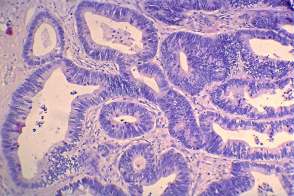

Histopathology: metastasis of a colon cancer to the thyroid.

• The less obvious failure was my cytological diagnosis. Knowing the final diagnosis, of course, I would say otherwise. And re-examining the cytology sample later helped to avoid a similar mistake. Although the cytological picture resembles that seen in papillary cancer, the cytological pattern should raise colonic cancer. The clue is the palisading arrangement of tumor cells.